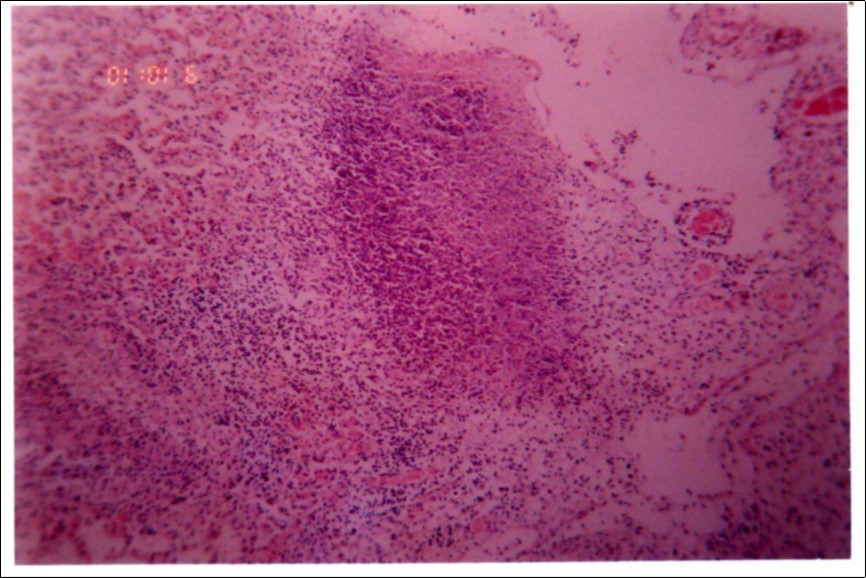

Figure 3, Figure 4 and Figure 5 show different histopathological pictures of hepatized lung tissue samples from which Mmm isolates were recovered. In Figure 3, widened interlobular septa, due to presence of fibrinous necrosis and cellular infiltration were observed. Figure 4 shows extensive loss of airspace due to necrosis and infiltration of neutrophils. Figure 5 shows hyperemia of alveolar wall capillaries and infiltration of few fibrin and neutrophils.

Figure 3.Widened interlobular septa in pneumonic lung tissue (H&E ×200).

Although no advanced techniques like PCR were used to identify the isolates, procedures used in this study were quite enough to confirm the incidence. Affected animals with CBPP were diagnosed based on the clinical signs, the PM findings, the typical histopathological picture in addition to the isolation of the causative agent and its subsequent identification using cultural and biochemical procedures. Identification of the isolates was confirmed by the growth inhibition test as recommended in OIE manual 10. The histopathological sections of diseased lungs, from which Mmm (SC) was isolated, showed typical histopathological picture of CBPP. The CBPP lesion comprises abronchiolar necrosis and oedema which progress rapidly to an exudative serofibrinous bronchiolitis with extension to the alveoli and uptake of alveolar fluid into tissue spaces 17, lymphatic vessels and ultimately septal lymphatics 18. With stasis, lymphatic vessels become thrombosed and ultimately fibrosed 19. The histological section of the lung in acute stage of the disease showed odema in the lymphatics of the interlobular septa and interstitial tissue and massive infiltration of fibrin, macrophage and neutrophils into the alveolar lumen 20. Also there was presence of lymphocytes and alveolar macrophages around the lymphatic vessels and septa margin 21. These findings supported the isolation results and gave additional evidence for the diagnosis of the disease.